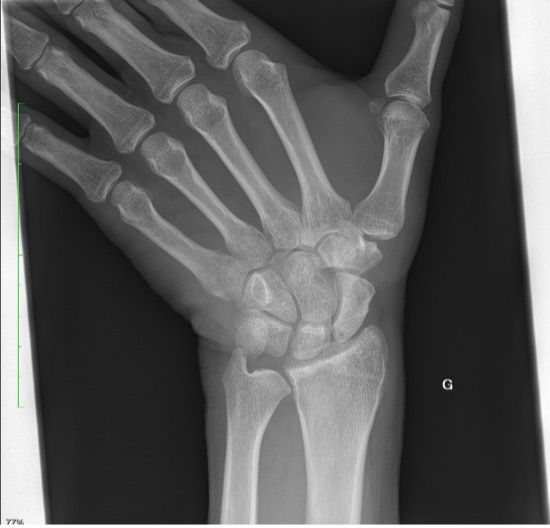

Un patient se présente pour des douleurs au niveau du poignet gauche, suite à une chute à vélo avec réception sur la paume de la main. Cliniquement, nous observons un œdème au niveau du dos de la main, des douleurs à la mobilisation du poignet avec une discrète limitation de l’extension et une prono-supination conservée.

La radiographie effectuée révèle une fracture du triquétrum. Les fractures du triquétrum (ou os pyramidal) sont les fractures du poignet les plus fréquentes après celles du scaphoïde, représentant 13% des fractures des os du carpe. Elles résultent habituellement d’une chute sur la main en hyperextension et déviation ulnaire. Elle est fréquemment retrouvée chez des pratiquant·es de sports de combat.

Il existe trois types de fractures du triquetrum : les fractures corticales dorsales, les fractures du corps et les fractures corticales palmaires. Pour ce patient, il s’agit d’une fracture de type 1 (95% des cas), qui est une fracture par avulsion associée à des lésions des ligaments dorsaux du carpe et considérée comme une « entorse grave du poignet ».

La clinique est aspécifique mais le diagnostic doit être évoqué face à des douleurs sur le côté ulnaire du carpe, après une chute main en extension. Les fractures du triquetrum passent facilement inaperçues sur les radiographies conventionnelles du poignet, mais elles sont souvent associées à des lésions ligamentaires importantes conduisant à une instabilité du carpe, ou évoluent vers une pseudarthrose. Un complément par CT (ou IRM) peut être nécessaire afin de confirmer le diagnostic et préciser les lésions.